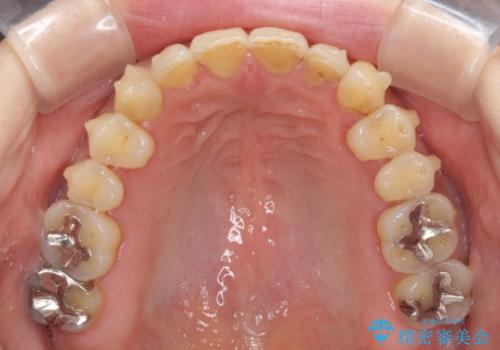

- 歯列不正と、どこで咬んで良いのか分からない咬み合わせを気にして来院された患者様です。

下顎骨は左側にシフトしており、咬み合ったときには奥歯と前歯の一部しか接触していない状態でした。

骨格的な左右差は歯列矯正は改善できないため、上下歯列が全体的に接触することをゴールとしてインビザラインにて矯正治療を行うこととしました。